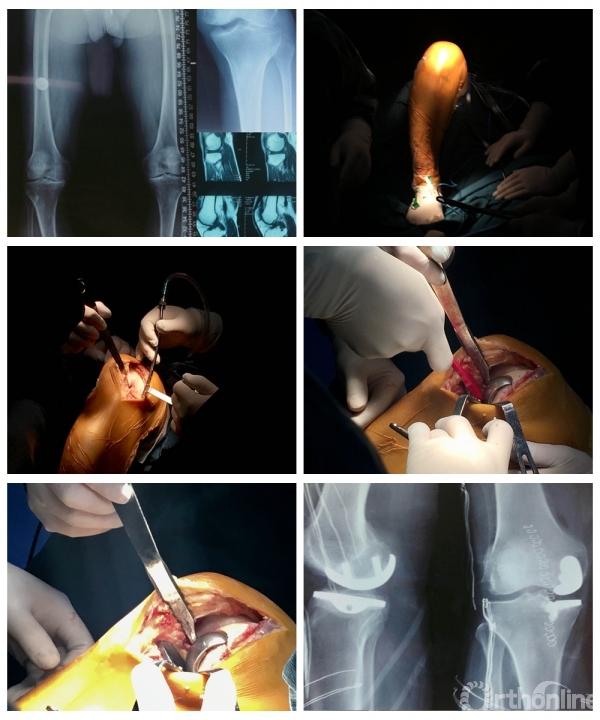

在两天的会议中,成功完成了11台手术,包括4台膝关节韧带重建、2台膝关节内侧骨关节炎单髁置换、1台肩关节前方复发性不稳定改良Bristow稳定术,1台巨大肩袖撕裂SCR修补、1台肩肩胛下肌冈上肌撕裂修补、1台跟腱痛风性腱病伴撕裂清理修补、1台距骨骨囊肿关节镜下清理植骨。

△手术现场

△手术名称:左膝前交叉韧带撕裂类等长重建 术者:陈世益教授

△手术名称:膝关节内侧骨关节炎单髁置换手术 术者:刘玉杰教授、戴雪松教授(两台手术)

△手术名称:前后交叉韧带重建 术者:李箭教授、张文涛教授(三台手术)